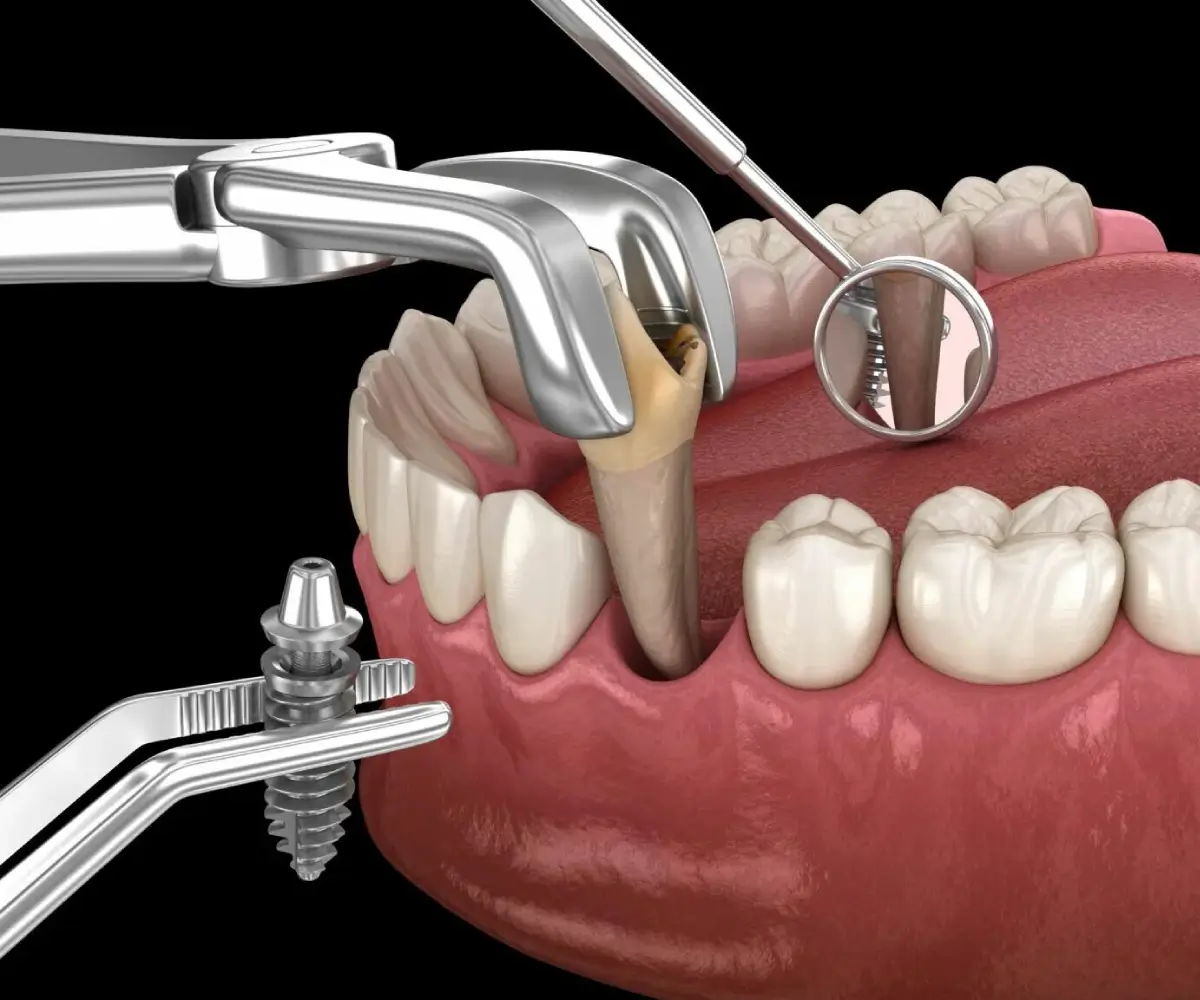

Immediate dental implants allow suitable patients to receive implant treatment with reduced waiting time following tooth removal. This approach can help restore appearance and function sooner while supporting a smoother and more efficient treatment experience.